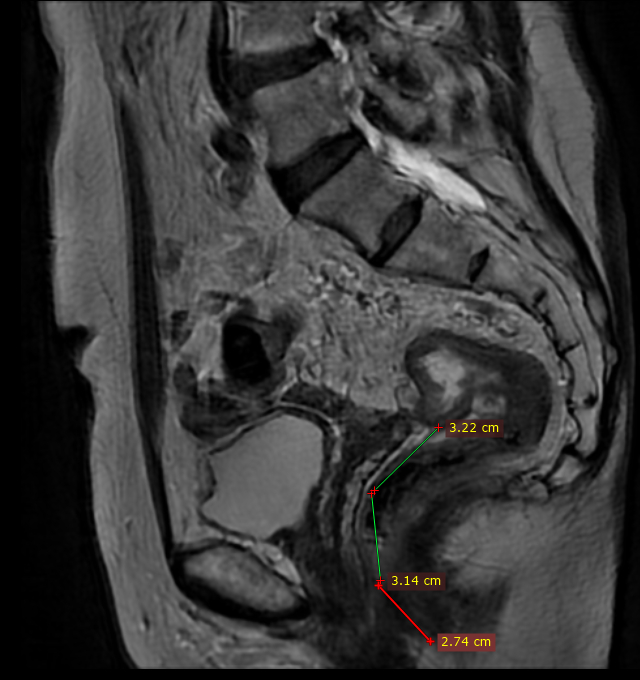

Год назад мне поставили страшный диагноз. Протоковый рак головки поджелудочной железы. Сама по себе болячка, ну, скажем, так себе…и осложнялось все тем, что были поражены прилегающие вены, артерии.

После прохождения 12 курсов химии эта гадость не уменьшилась, более того, мигрировала еще больше на артерии…Блохина и другие московские клиники, клиники Южной Кореи, Израиля, куда я отправляла свои СКТ и МРТ, признали опухоль неоперабельной - все отказывали в операции. Пипец был полный…

Единственная клиника, которая дала мне возможность ЖИТЬ – Ильинская больница в Москве и потрясающий доктор Егоров Вячеслав Иванович со своей супер командой супер профессиональных докторов! Мне была проведена операция по удалению опухоли, невероятно сложная, с реконструкцией вен и артерий. Мне сохранили жизненно важные органы!! Да, клиника платная, да, деньги собирали всем миром – родственники, друзья, бывшие однокурсники и одноклассники, моё байкерское сообщество, Банда, Вороны, все, кто мне помог собрать деньги - люблю вас всех бесконечно!!! - но жизнь дороже. Там – деньги не нужны…